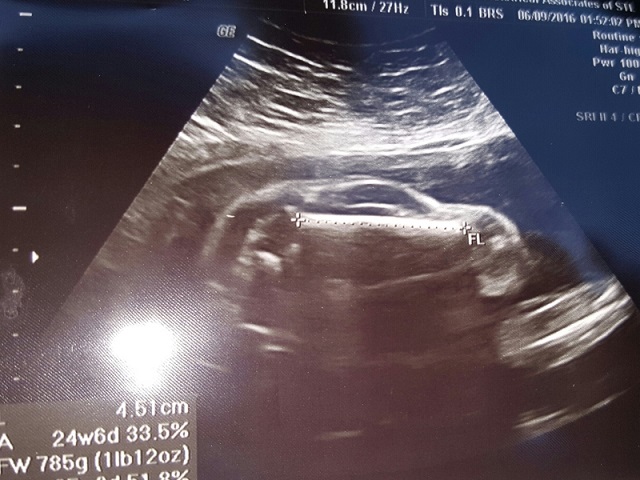

愛車的準爸爸若看到這一幕恐怕樂翻了!國外一對夫婦日前到婦產科進行胎兒掃描檢查,結果準媽媽腹中竟照出了一輛「車」的影像,有網友看過後大喊:「是下一個車神!」甚至建議把寶寶取名為車廠名稱,引發眾人熱烈討論。

美國一名準媽媽腹中竟照出了一輛「車」的影像。(圖片來源:techtimes)美國一名準媽媽腹中竟照出了一輛「車」的影像。(圖片來源:techtimes)

根據《techtimes》報導,美國密蘇里州這對夫婦看到照片後感到相當詫異,認為影像並不正常,但院方負責照超音波的醫師也無法解釋個所以然,只當是因巧合造成,猜測有可能是小嬰兒的大腿骨,但媽媽 Reena Roberts 則認為:「我知道這是一輛男孩子的車,一定是。」

準爸爸 Mike 則將這份喜悅分享到社群網站 Reddit 上,照片很快就吸引眾多車迷熱烈討論,有人看過後表示,「天啊,說不定是車神降臨了」、「還在肚子裡就挑好車了,這小子不簡單」、「太好玩了!沒看到還真的不相信啊」等,有人還開始猜測照片上究竟是哪家車廠的車款,像是 Ford、Porsche、M-Benz 等,甚至要夫妻倆挑一間車廠替孩子命名比較快。